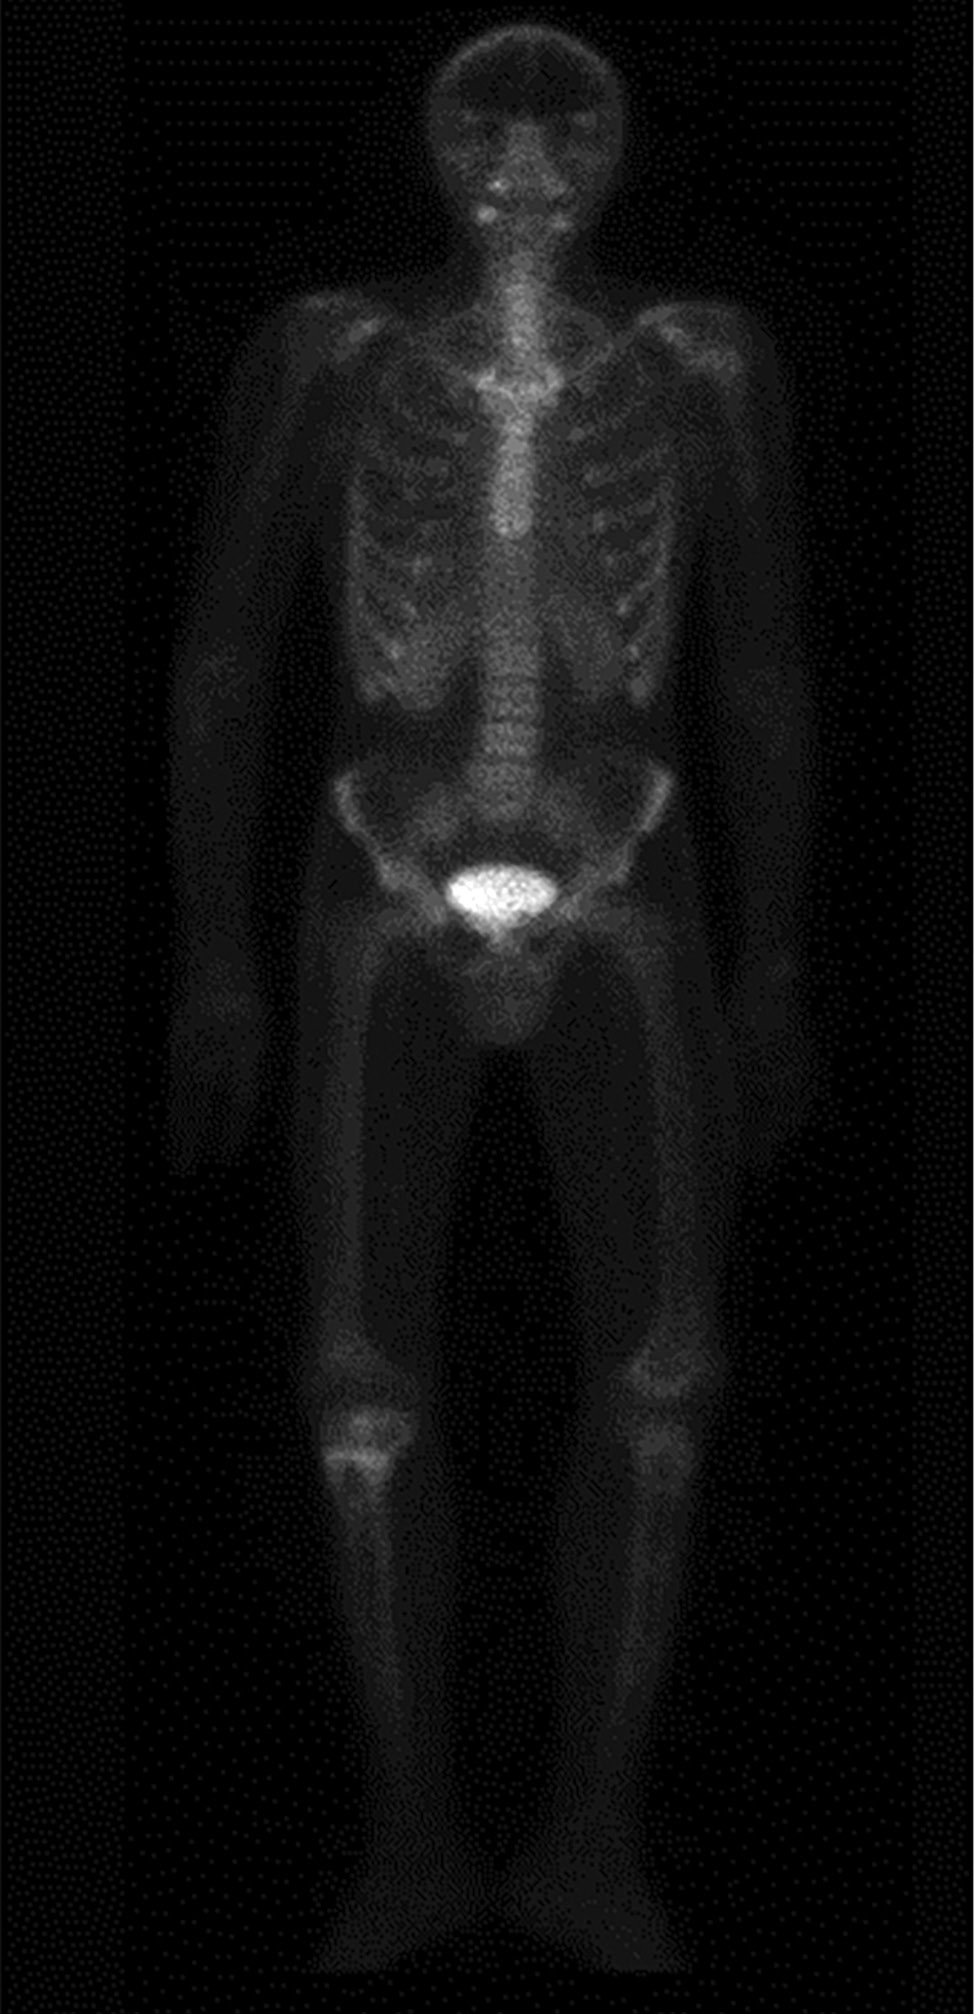

Для уточнения генеза костных нарушений и исключения метастатического поражения скелета по месту жительства проведена сцинтиграфия с Пирфотех 99mTc всего тела, по результатам которой наблюдались генерализованные остеобластические и остеолитические процессы в костной ткани (рис. 3). Пациент был осмотрен онкологом, проведена биопсия кистозных изменений правой большеберцовой и бедренной костей, по результатам которой получены фрагменты фиброзной ткани с включениями небольших очагов реактивного костеобразования, эпителиальная выстилка не определялась. Гистологически верифицированы костные кисты. Лабораторное исследование состояния фосфорно-кальциевого обмена в этот период времени не проводилось.

Рисунок 3. Однофотонная эмиссионная компьютерная томография с Пирфотех 99mTc всего тела: генерализованный остеобластический и остеолитический процессы в костной ткани, с наиболее выраженным проявлением в проксимальном метафизе правой большеберцовой кости.